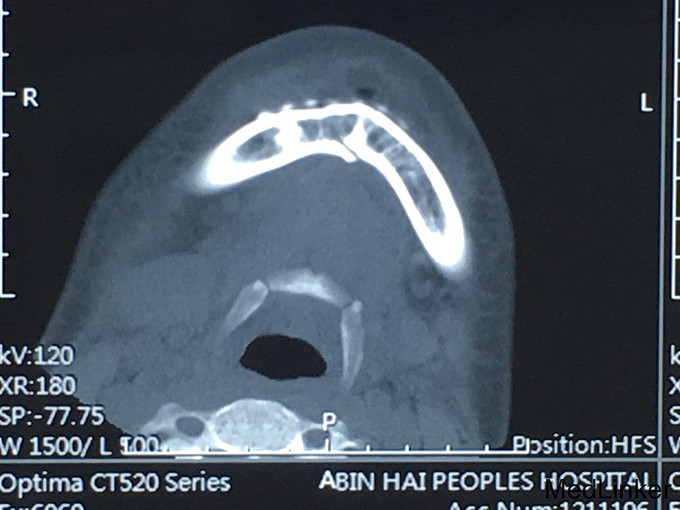

查体:神志清楚,右下颌体部见长约2.0cm开放创口,张口度1.5cm,咬合关系紊乱,右下唇麻木感,43,44间见明显骨折线,异常动度,48松动II,牙龈撕裂,右下颌肿胀,右侧髁状突冲击试验减弱,上颌骨无异常动度,于无异常。 辅查:CT,右下颌骨颏部及下颌角不骨折。

诊断:右下颌骨颏部及下颌角不骨折 治疗:右下颌骨颏部及下颌角部骨折经口内切开复位内固定。

随访:术中咬合恢复良好,被动张口度3.0cm,术后半年、1年、3年随访咬合良好,张口度正常水平。 讨论:下颌角部于外斜线处置接骨板,下缘无需再置接骨板。无需自口外颌下切口,避免损伤面神经下颌缘支。